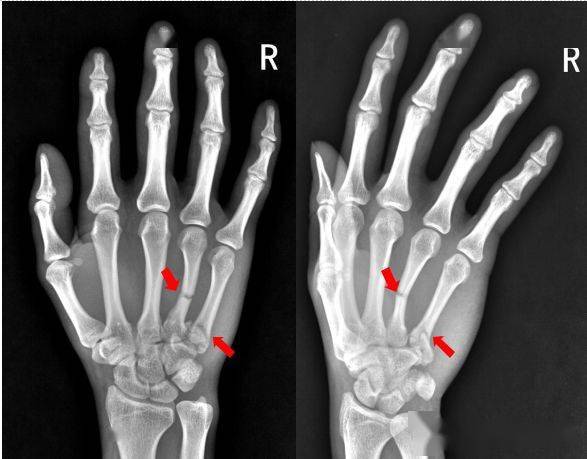

病例2,诊断为右手第五掌骨基底部骨折.

右手第五掌骨骨折(1-5.